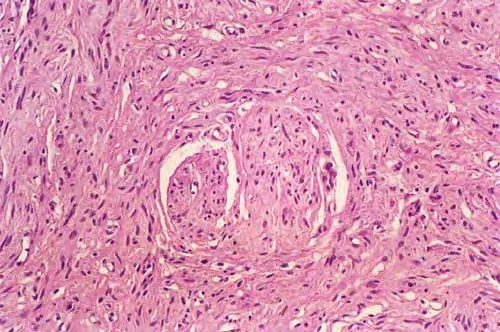

Neurofibroma = الليفوم العصبي